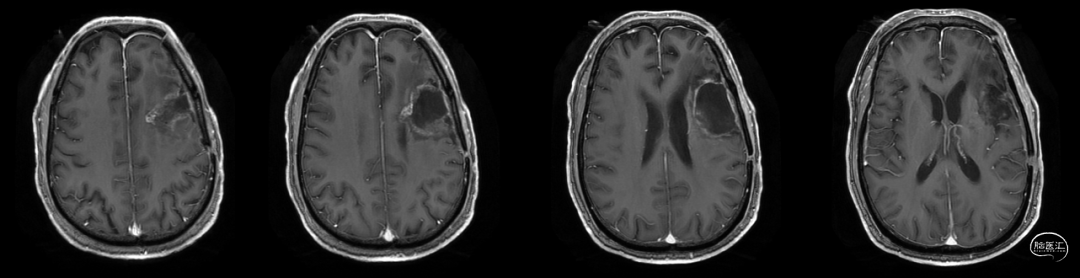

放疗后17月(2021-12-20)MRS显示左颞叶感兴趣区Cho/NAA约1.19-5.53:图示。

放疗后17月(2021-12-20)PWI显示感兴趣区脑血容量及血流量较对侧高低不一,平均通过时间及达峰时间延长,提示左侧病变区血流灌注降低:图示。

再次经MDT讨论,考虑假性进展可能,继续肿瘤电场治疗。

术后5周开始实施标准的新STUPP方案的辅助治疗,即在同步放化疗后,辅助替莫唑胺化疗的同时使用了电场治疗。目前生存25月,且临床和影像学表现均提示稳定,未见复发迹象。期间,在放疗后7月时复查MRI提示异常FLAIR信号区增大,经我院MDT讨论,考虑到强化信号减轻,无明显占位效应,患者无症状体征,考虑是治疗后水肿,非进展,故继续按原方案治疗。放疗后17月复查MRI出现术区边缘局部强化范围稍增大,但PWI示强化区局部呈低灌注且未见弥散受限表现,MDT讨论考虑为假性进展,继续原方案治疗。后续复查MRI强化范围减轻,证实了MDT的判断证实疾病稳定。患者生存时间已达25个月。全程安全顺利,仅出现一过性轻度皮肤反应。

辅助TMZ治疗过程中每2-3月复查MRI。治疗中曾出现水肿范围增大,尽管有部分区域弥散受限和MRS异常及血流量增加,但是临床症状未加重,仍继续原方案治疗,后续监测PWI显示病变区灌注减低。提示持续肿瘤电场治疗可以使病变长期稳定。此患者每天佩戴肿瘤电场治疗时间接近22小时,中间出现头皮发红和小水泡,经局部外用皮质类固醇和外用抗生素,暂停2天治疗恢复。至今随访25月稳定。说明肿瘤电场治疗联合TMZ治疗较单TMZ治疗明显延长胶质母细胞瘤患者PFS及OS,临床应积极推广使用。